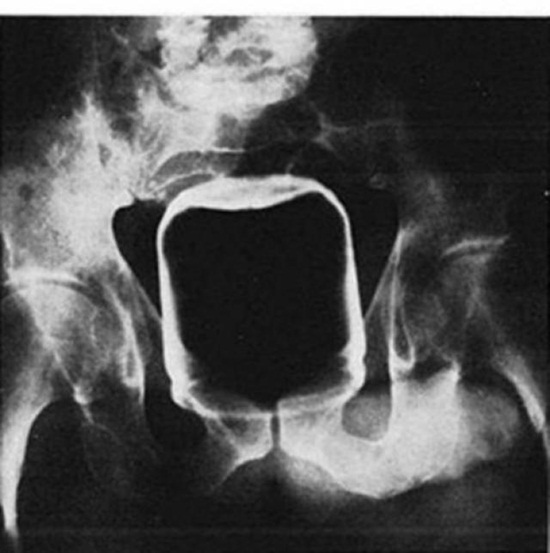

ปักพินในบอร์ด “Let’s Know” Infographic เอกซเรย์กระดูกโคนขา ภาพสต็อก – ดาวน์โหลดรูปภาพตอนนี้ – สะโพก – ส่วนของ …

เอกซเรย์กระดูกโคนขา ภาพสต็อก – ดาวน์โหลดรูปภาพตอนนี้ – สะโพก – ส่วนของ … เทคนิคการถ่ายภาพเอกซเรย์ซีทีด้วยปริมาณรังสีที่เหมาะสม – ร้านหนังสือ …

เอกซเรย์ ภาษาจีนคืออะไร | Wordy Guru เอกซเรย์กระดูกโคนขา ภาพสต็อก – ดาวน์โหลดรูปภาพตอนนี้ – สะโพก – ส่วนของ …

เอกซเรย์กระดูกโคนขา ภาพสต็อก – ดาวน์โหลดรูปภาพตอนนี้ – สะโพก – ส่วนของ … โรคหลอดเลือดหัวใจ (Coronary artery disease) อาการ สาเหตุ การรักษา ฯลฯ